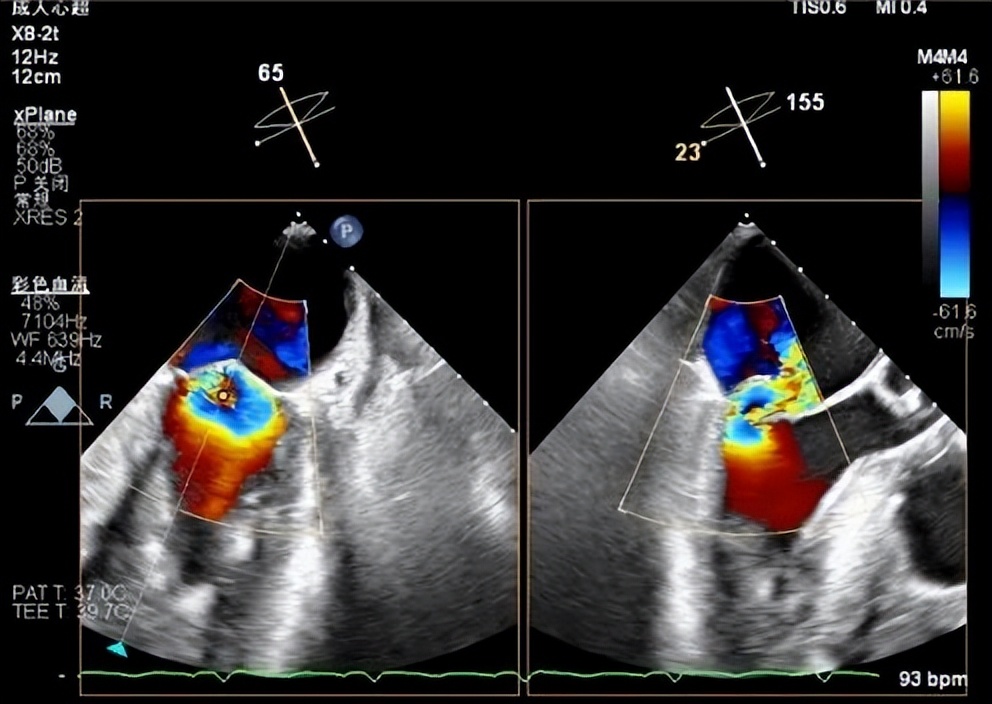

患者男性,71岁,反复心衰发作,心脏彩超示重度二尖瓣返流(MR 4+)(图二、三),既往糖尿病病史10余年、单侧颈内动脉闭塞7年余,2年前行冠脉搭桥及主动脉动脉瘤支架植入术,本次心衰急性发作合并严重肺部感染,经口气管插管呼吸机辅助并对症药物治疗,效果欠佳;存在较高心功能进一步恶化、呼吸循环衰竭、恶性心律失常、猝死等风险。

图二(食道超声心动图二尖瓣大量返流)

食道超声显示术后即刻效果显著,心房侧未见返流信号(图九),3D显示二尖瓣呈组织桥形态良好的双孔状,返流消失(图十),临床症状明显改善,术后效果堪称完美。

图九(左:术前大量反流 右:术后心房侧未见明显返流信号)